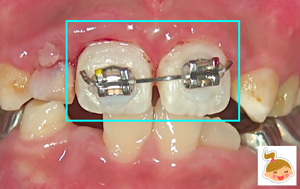

患者さんは、小学校4年生。主訴は「学校でこけて前歯をぶつけた。血が出てグラグラしている。唇も切れて腫れている」でした。 グラついて、出血している前歯2本は、大人の永久歯。そのお隣りの歯(乳歯)もグラついて抜けかけ。 前歯2本を固定するには、とても難しいケースでした。 口唇も腫れあがり視野の確保が易しくなかったため、矯正装置(保険治療)を利用して、短時間での強固定を試みました。1ヶ月間、このままの状態で経過をみる予定です。 泣かずによくがんばりました◎えらかったよ!